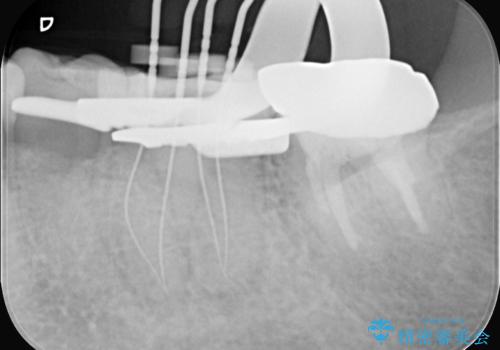

- 2日前から歯の痛みが続くという主訴でご来院されました。診察の結果、**不可逆性歯髄炎(歯の神経の重度の炎症)**と診断。レントゲンでは、歯髄腔が狭くなり、根管が石灰化している難症例であることが確認されました。患者様の大切な歯を残すため、歯科用顕微鏡を用いた精密根管治療を行うことで、狭く、見えにくい根管を正確に探し出し、治療を完了させる計画を立案しました。

今回の治療は、特に難易度の高い石灰化した根管が対象でした。まず、治療中の細菌感染を防ぐためにラバーダムを使用。次に、歯科用顕微鏡で治療部位を何十倍にも拡大しながら、狭窄した根管の入り口を探し、慎重に拡大・清掃を行いました。顕微鏡を用いることで、肉眼では不可能だった根管内部の細かい構造を確認しながら、感染源を徹底的に除去することができました。これにより、難症例の奥歯でも再発リスクを抑えた適切な処置を行うことができ、治療後に痛みは解消。大切な歯を長期間にわたり保存することができました。